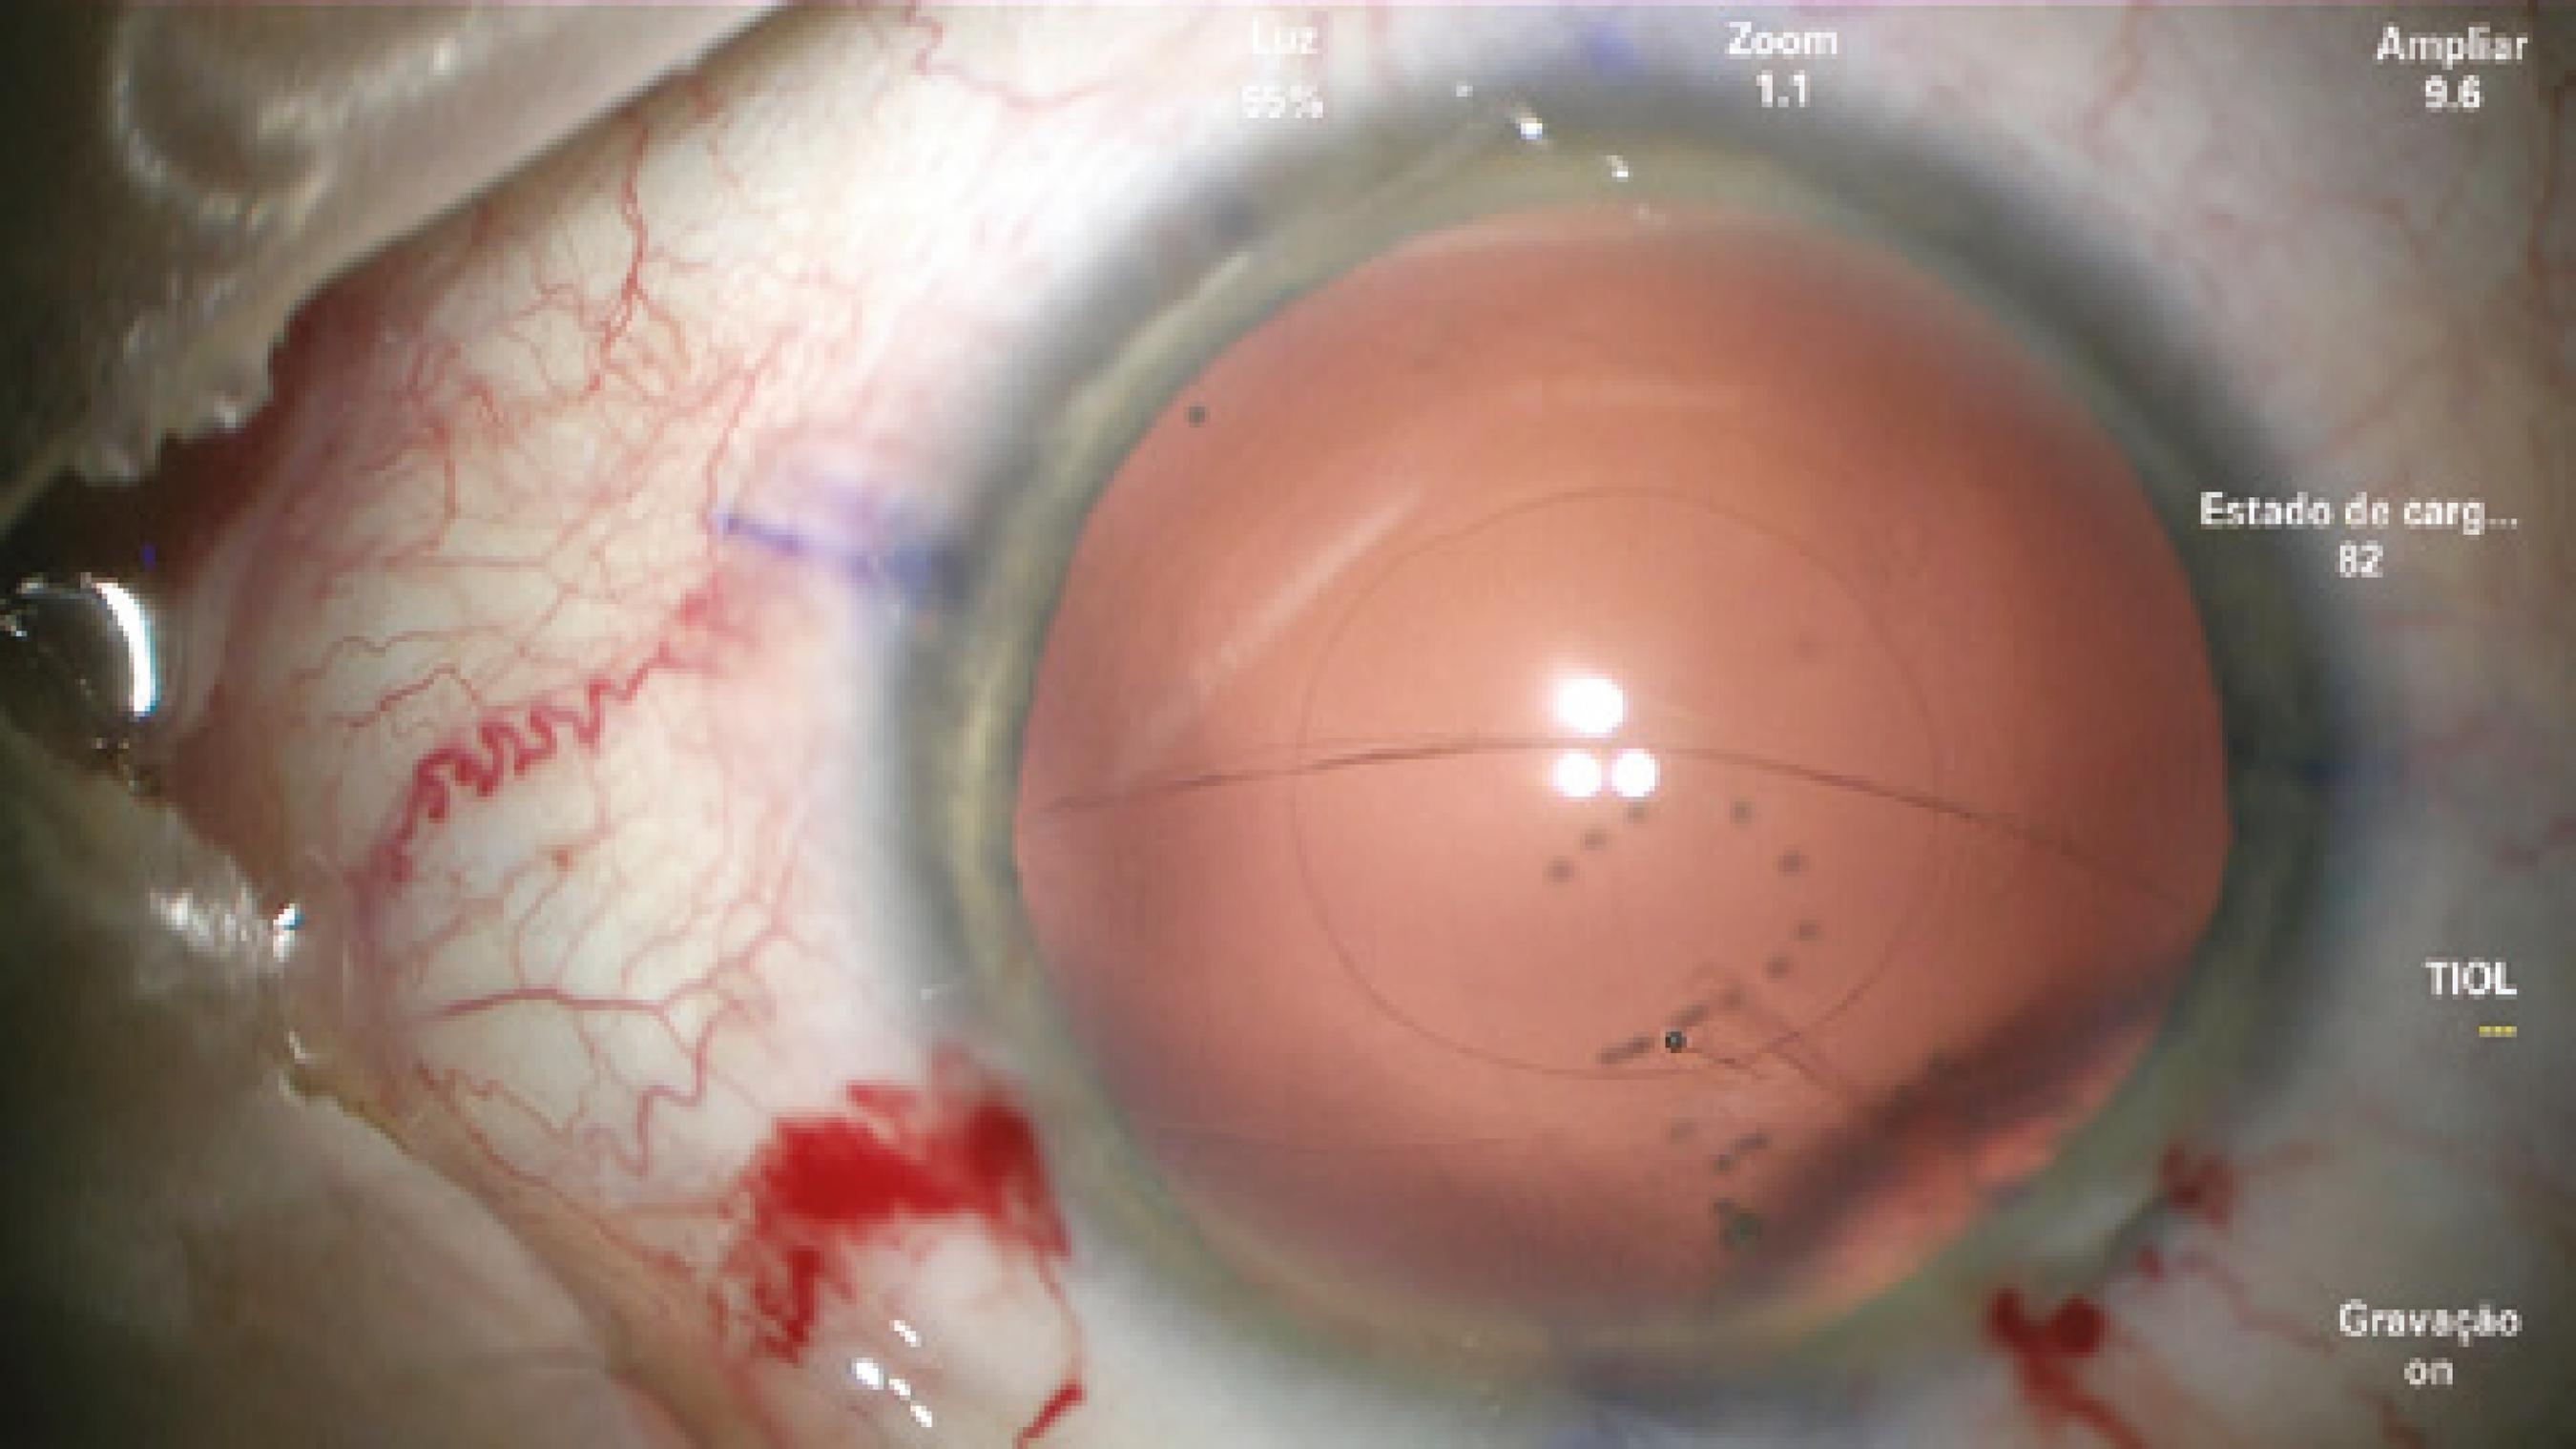

After confirming the 14-mm W-W diameter with calipers, phacoemulsification and cortical aspiration were performed without complications. To perform PCCC, the capsular bag was filled with a cohesive viscoelastic device (ProVisc®; Alcon Laboratories, Inc., Fort Worth, TX, USA). A 27-gauge needle mounted in a dispersive ophthalmic viscosurgical device (OVD; Viscoat®, Alcon Laboratories, Inc.) was used to perform the initial puncture of the central posterior capsule and inject dispersive viscoelastic into Berger's space to avoid rupture of the anterior hyaloid membrane (Figure 1). However, as soon as the posterior capsule was punctured, a tear extended spontaneously to the periphery in a similar fashion to an Argentinean-flag sign in the anterior capsule (Figure 2). Because the eye was well pressurized with a stable anterior chamber, the anterior hyaloid membrane remained intact and no vitreous humor prolapsed. IOL insertion into the capsular bag was performed using a bimanual technique with extreme caution to avoid extending the tear, vitreous humor prolapse, and dropping the IOL into the vitreous cavity.